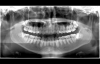

CTスキャンによる親知らず(下歯)の画像

親知らずとは、「第3大臼歯」とも呼ばれ、奥歯(臼歯)の一番奥に生える歯の事です。

通常上下左右に4本ずつあり、まれにきちんと生えてくる人もいますが、大体の場合他の歯とは別向きに生えたり歯茎に埋もれたまま成長したりします。

レントゲン撮影での歯の状態

上下左右に通常の歯並びとは明らかに違う歯が確認できる

レントゲン撮影でも下の歯の左右に横向きに生え、横の奥歯とがっちりかみ合って成長している親知らずが確認できます。

CTスキャンでの親知らず(右下)の様子

CTスキャンでも検査を行います。

左上の画像では奥歯の横にがっちりはまり込んでいる親知らずが確認できます。

赤い線は神経が通っている所

CTスキャンでは、親知らずの根のすぐ下に神経(下歯槽管)が通っている事が判明しました。

神経を傷つけない様に、慎重に抜歯を行う事が求められます。